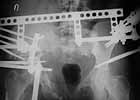

A female 27 years old admitted to our unit. Injured 18 month ago in a car accident. Initially the pelvis was fixed by anterior frame. 1 month later hardware was removed because of pin tract infection, and walk with cruches allowed. Also reptroperitoneal haematoma got infected.

Now there is shortening ~5 cm, no walking aids, of course obvious limp. No signs of infection neither clinically nor in lab tests. Which is optimal management for now? Only to move down the acetabulum (by which approach?), or full reduction of anterior and posterior aspects, acutely or gradually?